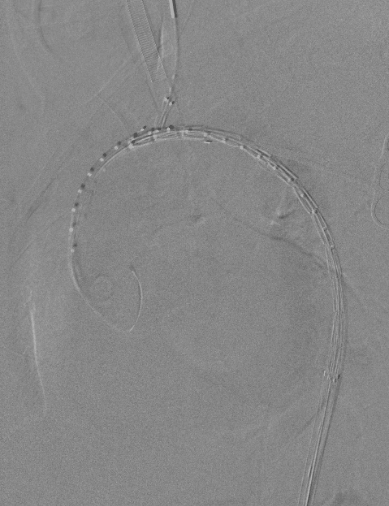

1、穿刺患者左肱动脉与右股动脉,并在左肱动脉置入5F的穿刺鞘后,导入软导丝,从右股动脉导入7F长鞘至降主动脉,交换超硬导丝与分支导丝并导入造影导管进行造影;

与长鞘并行导入造影导管

动脉长鞘怎么置入【弓部重建直通车】真腔难觅,另辟蹊径|潍坊市人民医院血管外科运用Castor®支架结合长鞘建立导丝通路治疗主动脉夹层两例_https://www.jmylbn.com_新闻资讯_第9张

术前造影